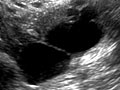

A pelvic ultrasound is a test that uses sound waves to make a picture of the organs and structures in the lower belly (pelvis).

Organs and structures that are solid and uniform (such as the uterus, ovaries, or prostate gland) or that are fluid-filled (such as the bladder) show up clearly on a pelvic ultrasound. Bones may block other organs from being seen. Air-filled organs, such as the intestines, can make the image less clear.

- Confirm a pregnancy and see if it is in the uterus. Pelvic ultrasound may be used early in pregnancy to check the age of the pregnancy or to find a tubal pregnancy (ectopic pregnancy) or multiple pregnancy.